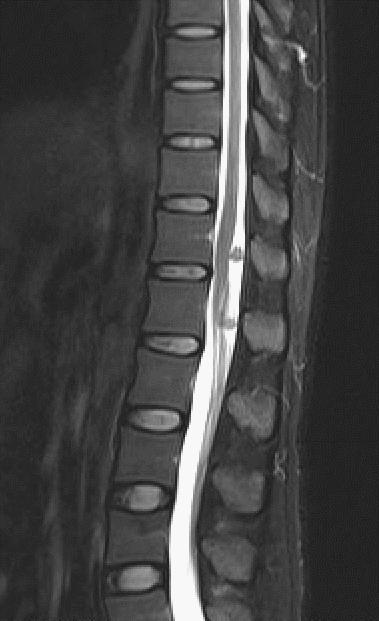

MRI

T1WI矢状位,定位图中所示最下一节为腰5椎体。T2WI、T2WI压脂、T2WI轴位、T1WI增强

E胸12 腰1椎体结节状异常信号,T1WI及T2WI高信号,压脂像及增强低信号

F脊髓见条形高信号,考虑水肿损伤